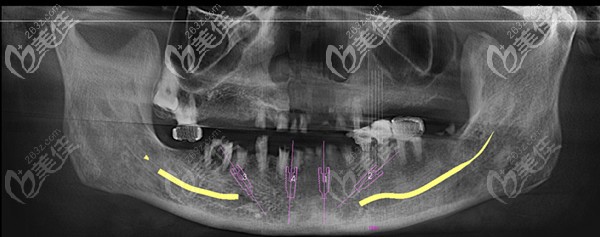

害怕種植體輕易穿透或掉入上頜竇內(nèi),可以用PCC做上頜竇提升種植手術(shù)

b2913 G0 V0

上頜竇提升種植牙手術(shù)對于種植來說,一直是屬于高難度的手術(shù)之一,所以一開始我們就要選擇好比較適合做上頜竇提升的種植體,那么就事半功倍了,今天來一起看看PCC為什么適合?